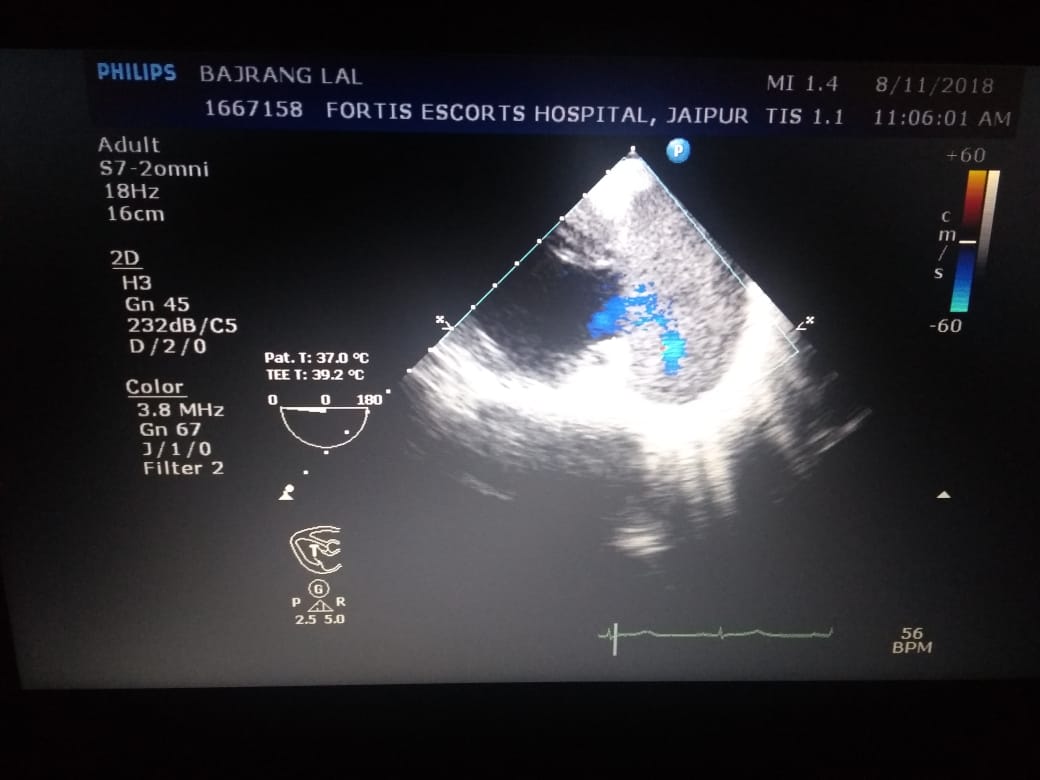

The patient, a known case of CAD & post PTCA, presented with acute limb ischaemia due to thrombus at

aortic bifurcation. On further investigation he was found to have CONTAINED RUPTURE OF LEFT

VENTRICLE WITH LARGE COMMUNICATING PSEUDOANEURYSM WITH CLOTS.